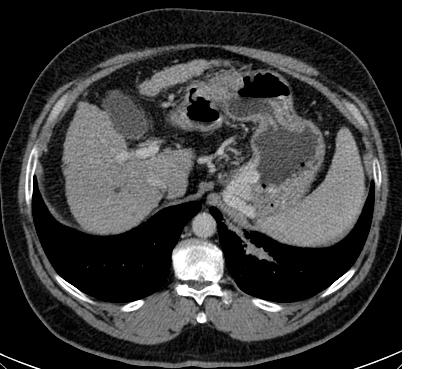

Signo de absceso hepático piógeno en la TC con contraste. En fase precoz se observa un área central hipodensa (el absceso) rodeada de un anillo denso (la pared realzada) –flecha verde- y una zona externa de baja densidad (edema) –flecha amarilla-.

Puede encontrarse otro ejemplo y más información en http://www.eurorad.org/eurorad/case.php?id=10428.